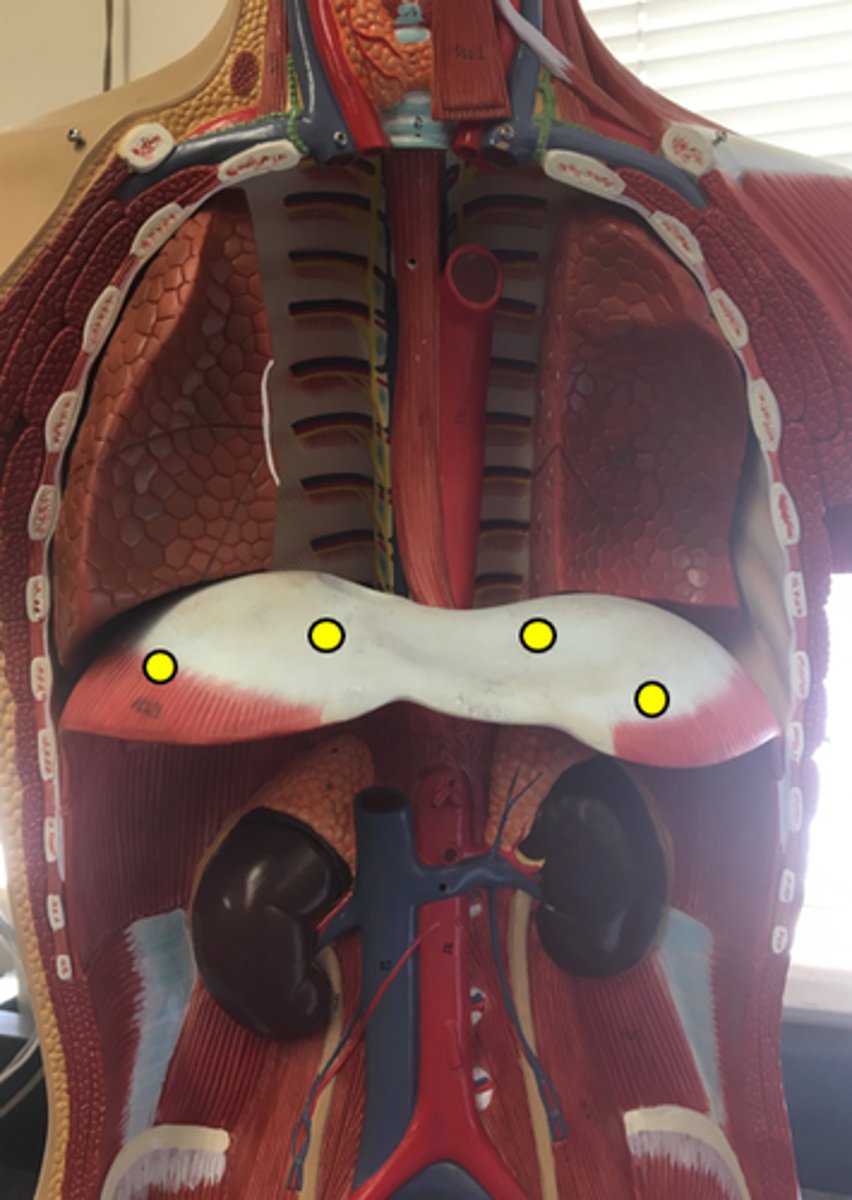

Diaphragm

External Intercostals

Internal Intercostals